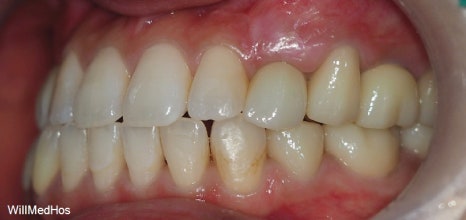

위의 사진이 최종 치료 사진 입니다. 뼈이식, 신경치료 후 크라운, 임플란트 치료를 진행 하였고

최종 기간은 10개월 정도 소요 되었습니다.

▲ 최종 완료 구강 사진